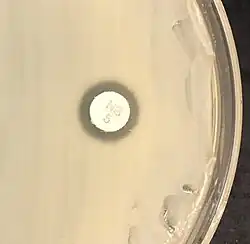

"S. saprophyticus" on Mueller–Hinton agar exhibiting resistance to novobiocin characteristic for species identification

Staphylococcus saprophyticus is identified as belonging to the genus Staphylococcus using the Gram stain and catalase test. It is identitified as a species of coagulase-negative staphylococci (CoNS) using the coagulase test. Lastly, S. saprophyticus is differentiated from S. epidermidis, another species of pathogenic CoNS, by testing for susceptibility to the antibiotic novobiocin. S. saprophyticus is novobiocin-resistant, whereas S. epidermidis is novobiocin-sensitive.[3]